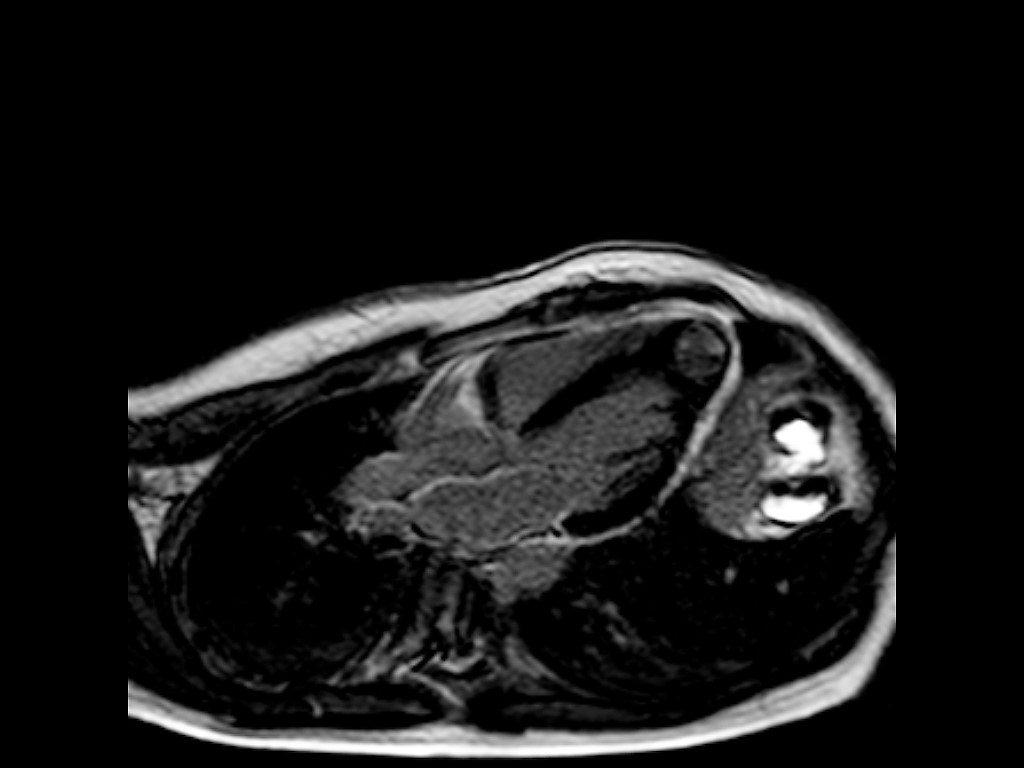

Se continuó estudios mediante RMI cardíaca observándose la misma cavidad contráctil observada en el ecocardiograma compuesta de las tres capas cardíacas. Se descartó la presencia de realce tardío de gadolinio. De esta manera se confirmó el diagnóstico de divertículo apical del VI.

RMI 1

RMI 2

RMI 3